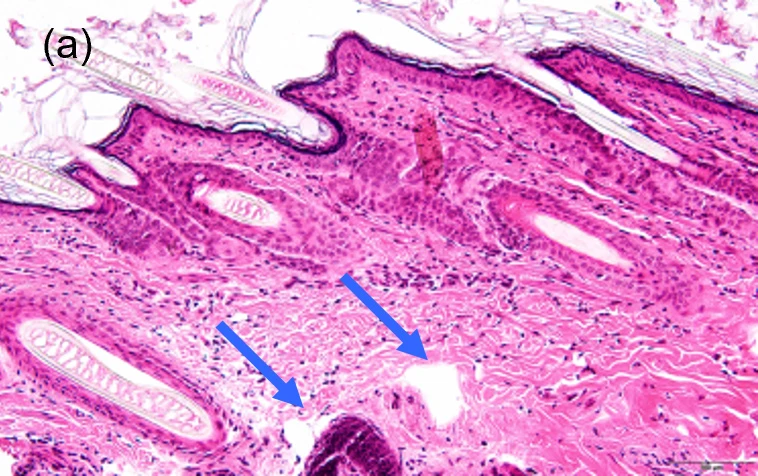

Хлоазма (мелазма) — это распространенное нарушение пигментации, чаще встречающееся у женщин с фототипами кожи по Фицпатрику III и выше. Хлоазма проявляется на участках кожи, подверженных воздействию солнечных лучей, в виде светло- или темно-коричневых неровных сливающихся пятен. Из-за ультрафиолетового излучения при хлоазме появляются такие гистологические изменения:

• повреждение базальной мембраны;

• «мигрирующие меланоциты»;

• сенесцентные фибробласты;

• патологическое разрастание сосудов1–5.

Сенесцентные клетки в основном наблюдаются в верхнем слое дермы, что облегчает взаимодействие с близлежащими меланоцитами. Повреждение базальной мембраны при хлоазме способствует взаимодействию сенесцентных фибробластов и эпидермальных меланоцитов. Это значит, что сенесцентные фибробласты могут способствовать усилению хлоазмы, и терапия, ориентированная на дерму, может рассматриваться в качестве метода лечения хлоазмы7.

Меланоциты в пораженной хлоазмой коже более крупные, у них более выраженные дендриты по сравнению с меланоцитами непораженной кожи, и они выступают в дерму. Мигрирующие меланоциты — характерная особенность хлоазмы. Точный механизм миграции меланоцитов при хлоазме неясен. Однако результаты исследований показывают, что повреждение базальной мембраны за счет увеличения экспрессии MMP2 и ММР9 может способствовать миграции меланоцитов9.

1. Kang WH, Yoon KH, Lee ES, Kim J, Lee KB, Yim H, et al. Melasma: histopathological characteristics in 56 Korean patients. Br J Dermatol 2002;146:228-37.

3. Torres-Álvarez B, Mesa-Garza IG, Castanedo-Cázares JP, Fuentes-Ahumada C, Oros-Ovalle C, Navarrete-Solis J, et al. Histochemical and immunohistochemical study in melasma: evidence of damage in the basal membrane. Am J Dermatopathol 2011;33:291-5.